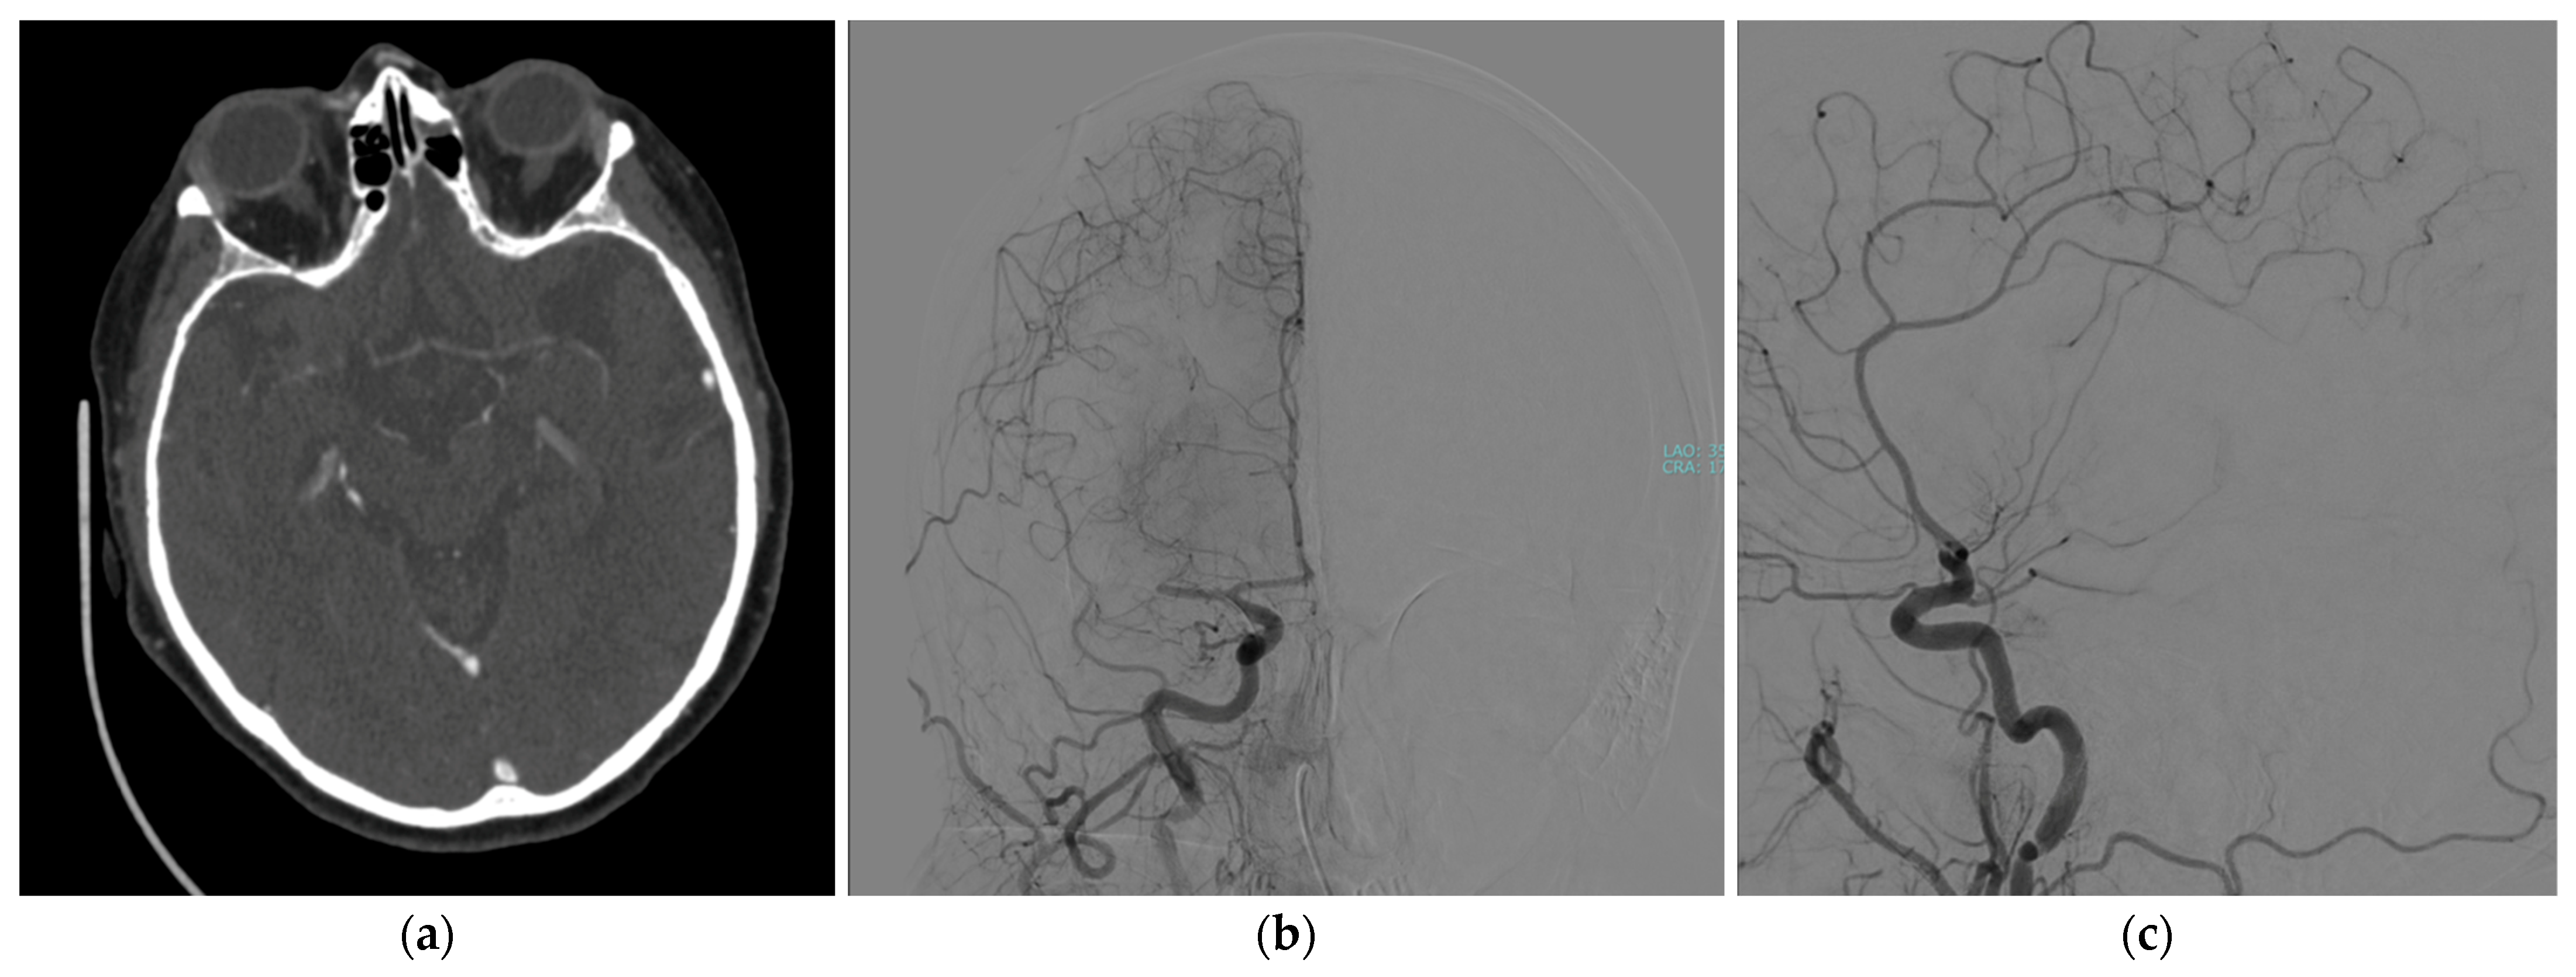

2. Case Presentation